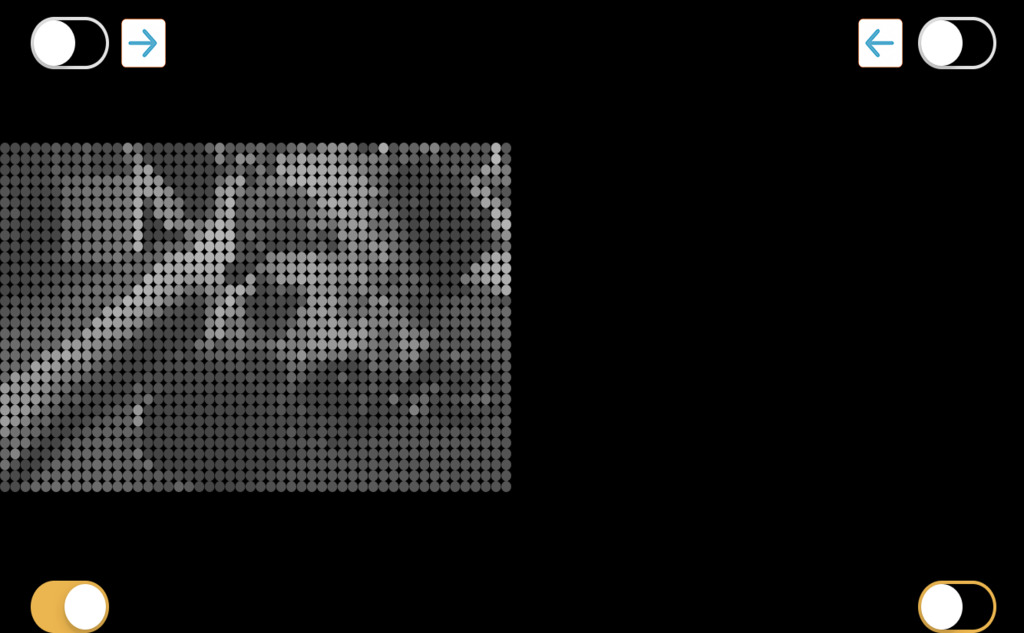

В приложении также есть специальная функция симуляции бионического зрения. С помощью See My World вы можете оценить уровень современных зрительных имплантов и узнать, как они работают. В приложении есть симуляция трех разных имплантов.

Но при тяжелых заболеваниях помогают только высокотехнологичные и дорогостоящие технологии – генная терапия или протезирование глаза специальными имплантами.

Чтобы поддержать исследования и разработки, которые помогут незрячим и слабовидящим, команда лаборатории «Сенсор-Тех» при участии Фонда президентских грантов запустила проект «Как вернуть зрение? Бионические зрительные протезы и виртуальная реальность».

Приложение See My World – это часть проекта. Также специалисты создали первый в России VR-симулятор, который позволяет любому желающему «примерить» на себя имплант сетчатки и увидеть мир «бионическим зрением».